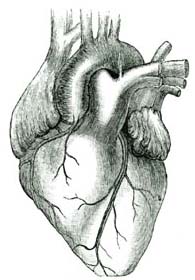

1. If you place your hand on the left side of your chest, you will feel something beating. If you cannot feel the beats easily, you may run up and down stairs two or three times, and then you can feel them very distinctly. How many of you know the name of this curious machine inside the chest, that beats so steadily? You say at once that it is the heart.

2. The Heart.—The heart may be called a live pump, which keeps pumping away during our whole lives. If it should stop, even [Pg 49]for a minute or two, we would die. If you will place your hand over your heart and count the beats for exactly one minute, you will find that it beats about seventy-five or eighty times. When you are older, your heart will beat a little more slowly. If you count the beats while you are lying down, you will find that the heart beats more slowly than when you are sitting or standing. When we run or jump, the heart beats much harder and faster.

3. Why the Heart Beats.—We have learned in preceding lessons that the digested food is taken into the blood. We have also learned that both water and oxygen are taken into the blood. Thus the blood contains all the materials that are needed by the various parts of the body to make good the wastes that are constantly taking place. But if the blood were all in one place it could do little good, as the new materials are needed in every part of the body. There has been provided a wonderful system of tubes running through every part of the body. By means of these tubes the blood is carried into every part where it is required. These tubes are connected with the heart. When the heart beats, it forces the blood through the tubes just as water is forced through a pipe by a pump or by a fire-engine.

[Pg 50]4. The Heart Chambers.—The heart has four chambers, two upper and two lower chambers. The blood is received into the upper chambers, and is then passed down into the lower chambers. From the lower chambers it is sent out to various parts of the body.

5. The Blood-Vessels.—The tubes through which the blood is carried are called blood-vessels. There are three kinds of blood-vessels. One set carry the blood away from the heart, and are called arteries (ar'-te-ries). Another set return the blood to the heart, and are called veins. The arteries and veins are connected at the ends farthest from the heart by many very small vessels. These minute, hairlike vessels are called capillaries (cap'-il-la-ries).

6. The Arteries.—An artery leads out from the lower chamber of each side of the heart. The one from the right side of the heart carries the blood only to the lungs. The one from the left side of the heart carries blood to every part of the body. It is the largest [Pg 51]artery in the body, and is called the aorta. Soon after it leaves the heart the aorta begins to send out branches to various organs. These divide in the tissues again and again until they become so small that only one corpuscle can pass through at a time, as shown in the colored plate. (Frontispiece.)

7. The Veins.—These very small vessels now begin to unite and form larger ones, the veins. The small veins join to form larger ones, until finally all are gathered into two large veins which empty into the upper chamber of the right side of the heart. The veins which carry blood from the lungs to the heart empty into the upper chamber of the left side of the heart.

8. What is Done in the Blood-Vessels.—While the blood is passing through the small blood-vessels in the various parts of the body, each part takes out just what it needs to build up its own tissues. At the same time, the tissues give in exchange their worn-out or waste matters. The red blood corpuscles in the capillaries give up their oxygen, and the blood receives in its stead a poisonous substance called carbonic-acid gas.

9. Red and Blue Blood.—While in the arteries the blood is of a bright red color; but while it is passing through the capillaries the color [Pg 52]changes to a bluish red or purple color. The red blood is called arterial blood, because it is found in the arteries. The purple blood is called venous blood, because it is found in the veins. The loss of oxygen in the corpuscles causes the change of color.

10. Change of Blood in the Lungs.—Exactly the opposite change occurs in the blood when it passes through the lungs. The blood which has been gathered up from the various parts of the body is dark, impure blood. In the lungs this dark blood is spread out in very minute capillaries and exposed to the air. While passing through the capillaries of the lungs, the blood gives up some of its impurities in exchange for oxygen from the air. The red corpuscles absorb the oxygen and the color of the blood changes from dark purple to bright red again. The purified blood is then carried back to the upper chamber of the left side of the heart through four large veins. The blood is now ready to begin another journey around the body.

11. The Pulse.—If you place your finger on your wrist at just the right spot, you can feel a slight beating. This beating is called the pulse. It is caused by the movement of the blood in the artery of the wrist at each beat of the heart. The pulse can be felt at the neck and in other [Pg 53]parts of the body where an artery comes near to the surface.

12. How much Work the Heart Does.—The heart is a small organ, only about as large as your fist, and yet it does an amount of work which is almost beyond belief. Each time it beats, it does as much work as your arm would do in lifting a large apple from the ground to your mouth. It beats when we are asleep as well as when we are awake. When we run we know by the way in which it beats that it is working very fast. Do you know how much a ton is? Well, in twenty-four hours the heart does as much work as a man would do in lifting stones enough to weigh more than one hundred and twenty tons.